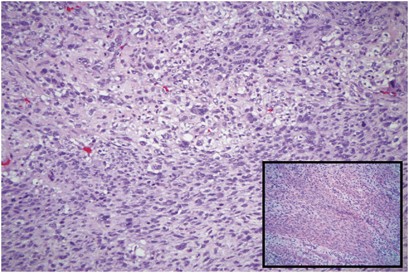

Depending on definitional criteria, UPS still accounts for a significant proportion of sarcomas occurring in late adult life. It manifests a broad range of histologic appearances, although the most common form consists of a mixture of storiform and pleomorphic areas.

Microscopically, the classic form of UPS has a highly variable morphologic pattern and shows frequent transitions from storiform to pleomorphic areas, although the emphasis in most tumors is on haphazardly arranged pleomorphic zones. Storiform areas consist of plump spindle cells arranged in short fascicles in a cartwheel, or storiform, pattern around slit-like vessels. Although such tumors resemble dermatofibrosarcoma protuberans, they differ by a less distinctive storiform pattern and by the presence of occasional plump histiocytic cells, numerous typical and atypical mitotic figures, and secondary elements including xanthoma cells and chronic inflammatory cells. Although this pattern is easily recognized, it is seldom seen throughout the entire tumor. Instead, most tumors have a combination of storiform and pleomorphic areas, with a preponderance on the latter. Least often, tumors have a fascicular growth pattern and resemble fibrosarcomas, except for scattered giant cells, and it may be an arbitrary distinction in some cases as to whether a given tumor should be designated as a UPS or fibrosarcoma. In contrast to the storiform areas, pleomorphic areas contain plumper fibroblastic cells and more rounded histiocyte-like cells arranged haphazardly with no particular orientation to vessels. Pleomorphism and mitotic activity are usually more prominent.

The stroma and secondary elements vary considerably in the storiform and pleomorphic areas. Usually, the stroma consists of delicate collagen fibrils encircling individual cells but occasionally collagen deposition is extensive and widely separates cells. Rarely, the stroma contains metaplastic osteoid or chondroid material. If, however, bone or cartilage is extensive and/or appears immature, the tumor should be classified as an osteo- or chondrosarcoma. The vasculature, although elaborate, is seldom appreciated unless it becomes dilated and resembles that of a hemangiopericytoma.

Some examples of this tumor have numerous giant cells, a lesion formerly referred to as the giant cell type of MFH or malignant giant cell tumor of soft parts.17, 18 These tumors tend to be distinctly multinodular and composed of a mixture of spindled, rounded, and osteoclast-type giant cells. Dense fibrous bands containing vessels often encircle the nodules, which frequently show secondary hemorrhage and necrosis. The cells display pleomorphism and prominent mitotic activity, and may contain ingested material such as lipid or hemosiderin. The nuclei of the osteoclast-type giant cells tend also to be of high nuclear grade. Focal osteoid or mature bone is present in up to 50% of these cases and is usually located at the periphery of the tumor nodules.